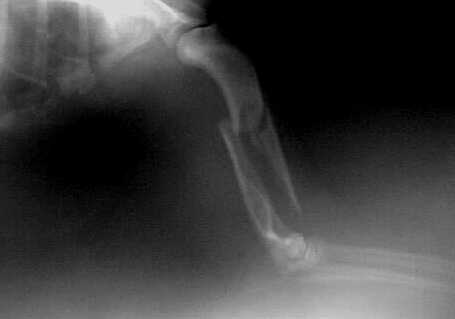

Elle-Speichen-Fraktur

paraossäre Klammer-Cerclage-Stabilisierung